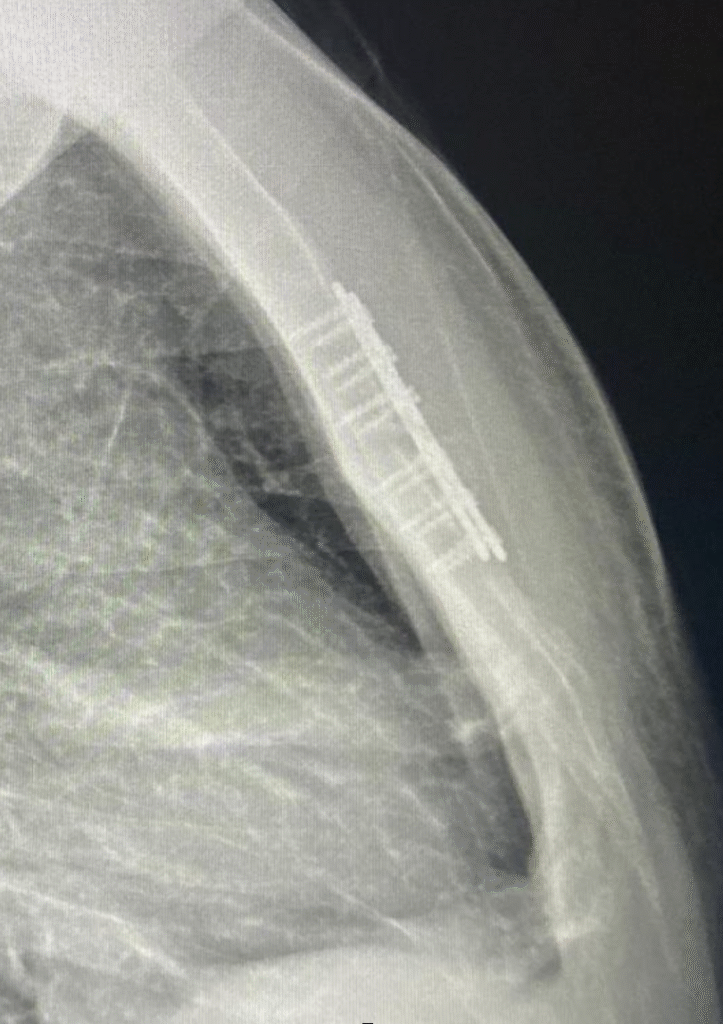

Ameliyat sırasında, sternum (iman tahtası) ile kaburgalar arasındaki düzensiz kıkırdak segmentleri çıkarılır,

ardından sternum doğru anatomik konumuna getirilir ve gerekirse destekleyici materyallerle stabilize edilir.